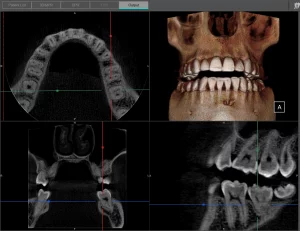

A CBCT was taken after a negative cold test indicated a necrotic tooth. When the CBCT was taken, we could clearly see that the abscess had completely perforated the labial bone at the apex of #24 and was close to doing so on #25.

As we investigated more deeply, we identified another critical piece of information that would affect our treatment plan: a second canal on #24.